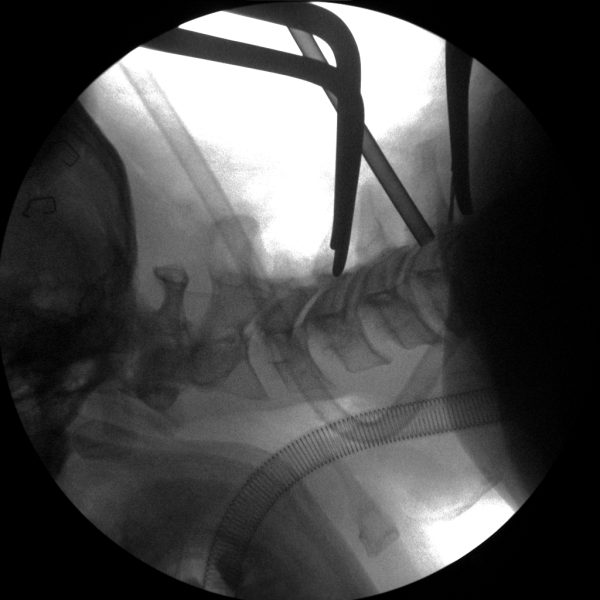

Neurosurgery demands the utmost precision and accuracy to ensure successful outcomes for patients.

Skan-C uses advanced imaging technology, such as pulsed fluoroscopy and digital subtraction angiography, to provide highly detailed images of the affected area. This allows doctors to perform procedures with increased precision and accuracy, and better patient outcome